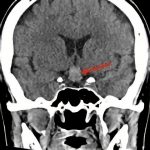

断層撮影

手術前2